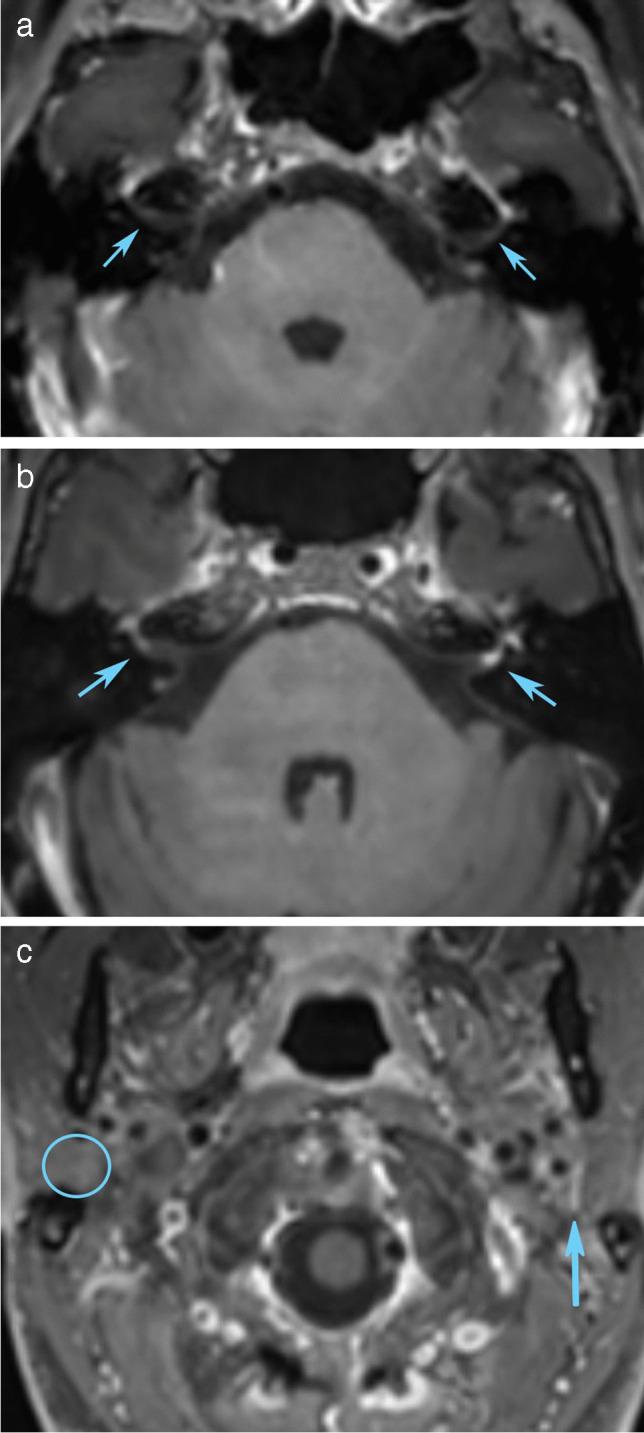

Symptoms of cranial neuritis are a common presentation of Lyme neuroborreliosis (LNB). Imaging studies are scarce and report contradictory low prevalence of enhancement compared to clinical studies of cranial neuropathy. We hypothesized that MRI enhancement of cranial nerves in LNB is underreported, and aimed to assess the prevalence and clinical impact of cranial nerve enhancement in early LNB.

In this prospective, longitudinal cohort study, 69 patients with acute LNB were examined with MRI of the brain. Enhancement of cranial nerves III-XII was rated. MRI enhancement was correlated to clinical findings of neuropathy in the acute phase and after 6 months.

Thirty-nine of 69 patients (57%) had pathological cranial nerve enhancement. Facial and oculomotor nerves were most frequently affected. There was a strong correlation between enhancement in the distal internal auditory canal and parotid segments of the facial nerve and degree of facial palsy (gamma = 0.95, p < .01, and gamma = 0.93, p < .01), despite that 19/37 nerves with mild-moderate enhancement in the distal internal auditory canal segment showed no clinically evident palsy. Oculomotor and abducens nerve enhancement did not correlate with eye movement palsy (gamma = 1.00 and 0.97, p = .31 for both). Sixteen of 17 patients with oculomotor and/or abducens nerve enhancement had no evident eye movement palsy.

MRI cranial nerve enhancement is common in LNB patients, but it can be clinically occult. Facial and oculomotor nerves are most often affected. Enhancement of the facial nerve distal internal auditory canal and parotid segments correlate with degree of facial palsy.